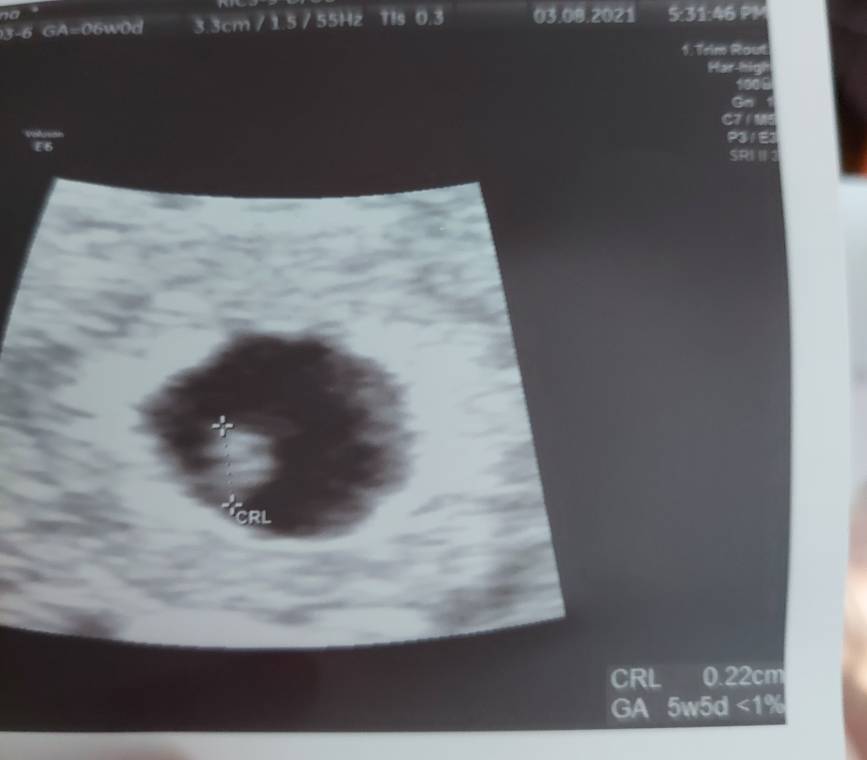

Mój Bobo ma już 2,2 mm [emoji2][emoji2][emoji2]

Jak się okazało, ciąża jest starsza niż myślałam, bo z usg wychodzi 5+5.

Termin prawdopodobnie 31 marca, ale jeśli pozwolicie zostanę z Wami [emoji173]